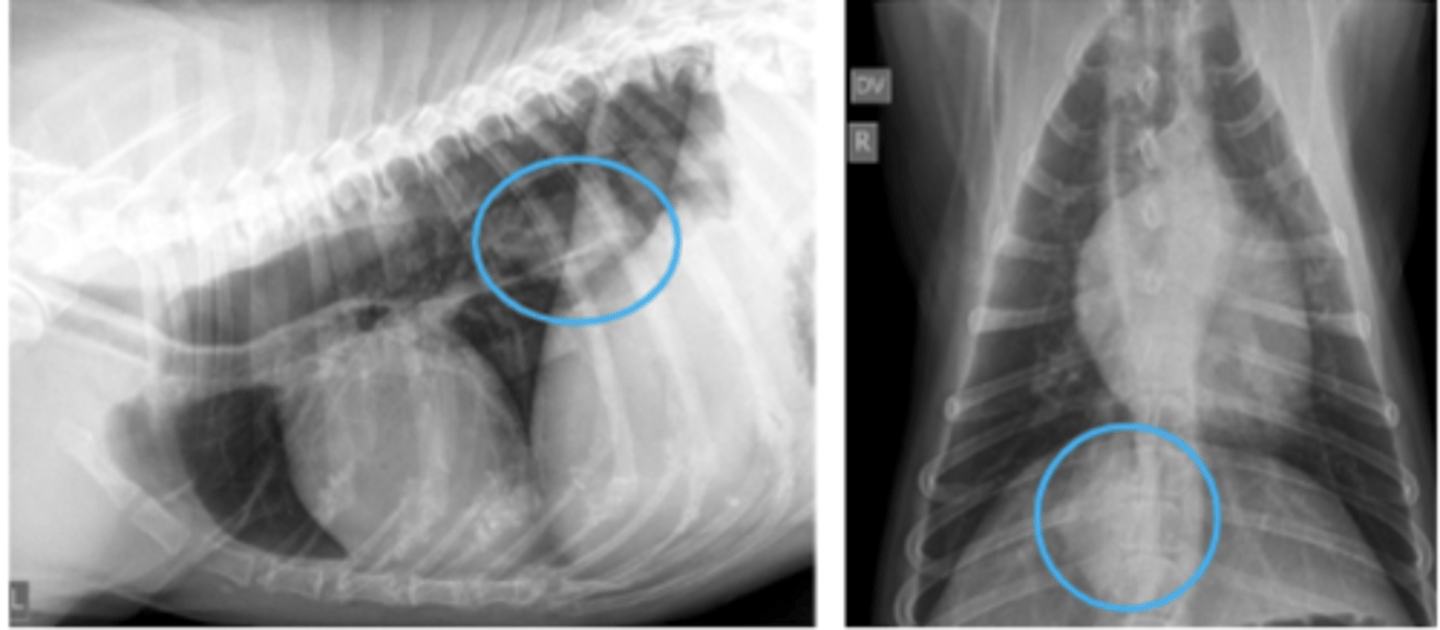

masa mediastínica craneoventral

- desplazamiento cd corazón

- desplazamiento tráquea derecha y dorsal

patología:

masa mediastínica craneodorsal

- desplazamiento ventral y/o derecha de la tráquea y corazón

masa hiliar/perihiliar

- ↑ densidad perihiliar

- se acentúa la flexión ventral de la tráquea distal

- desplaz. dorsal de la tráquea craneal

masa mediastínica caudodorsal

- desplaz esofágico/ compresión de su luz

- signo silueta con el diafragma

masa mediastínica caudoventral

- desplaz y/o compresión de la vena cava craneal

- signo silueta con el borde caudal del corazón y/o diafragma